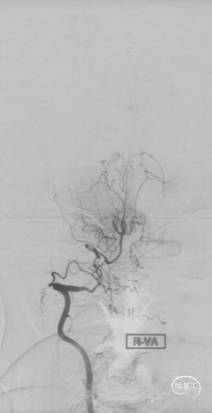

CTA和DSA

CTA和DSA所见:双侧颈内动脉闭塞,右侧椎动脉发出PICA后闭塞,左侧椎动脉V1-V2段闭塞。两条健壮的侧枝通过肌支吻合汇入左椎动脉V2段,构成了整个大脑大部分供血的主要来源。双侧颈外动脉亦有少量血流供应颅内。这样的颅内供血很容易发生失代偿,导致TIA甚至脑梗。